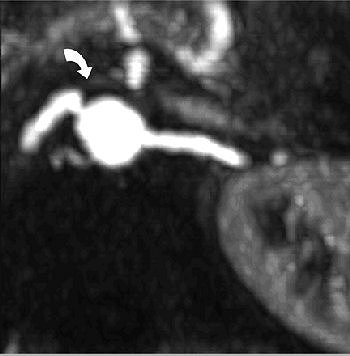

| Same patient as above. Digital subtraction angiography image that was insufficiently angulated does not show stenosis of ostium (arrow). Kock MCJM, Ijzermans JNM, Visser K, Hussain SM, Weimar W, Pattynama PMT, Krestin GP, Hunink MGM, "Contrast-Enhanced MR Angiography and Digital Subtraction Angiography in Living Renal Donors: Diagnostic Agreement, Impact on Decision Making, and Costs" (AJR 2005;185:448-456). |